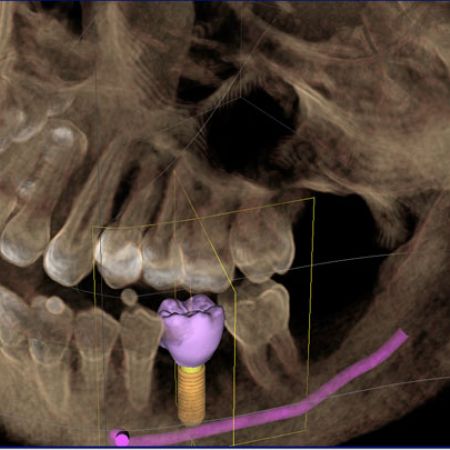

È una vite di titanio che viene inserita nell’osso sulla quale, atteso il periodo di guarigione, è possibile costruire restauri protesici. In altre parole l’impianto funge da “radice artificiale” e su di essa verrà costruita la corona (capsula) del tutto indistinguibile da una corona su un dente naturale.

Quando manca l’osso